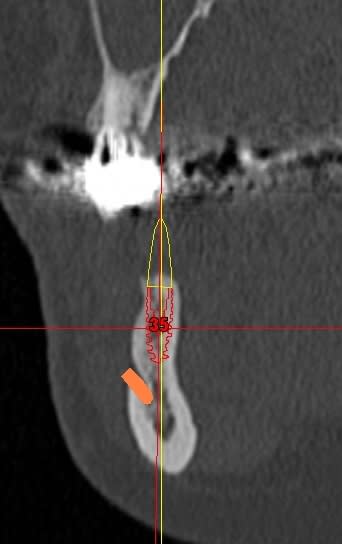

Effectivement le secteur 3 est curieux radiologiquement mais il y a des raisons ... l'expansion à la mandibule, fut...sportive.

Par contre, la réhabilitation du secteur 3 semble "curieuse''

Bonjour, pour la 16 ,tu peux faire une ostéotomie de SUmmers, tu as plus de 4 mm d'os .

Pour la 12 ou 13 utilise les expanseurs, prévoit un 3,6